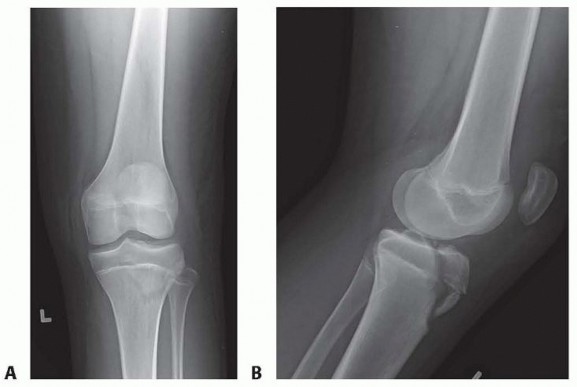

Chapter 28 Distal Femoral Physeal Fractures Martin J. Herman DEFINITION Fractures of the distal femoral physi…